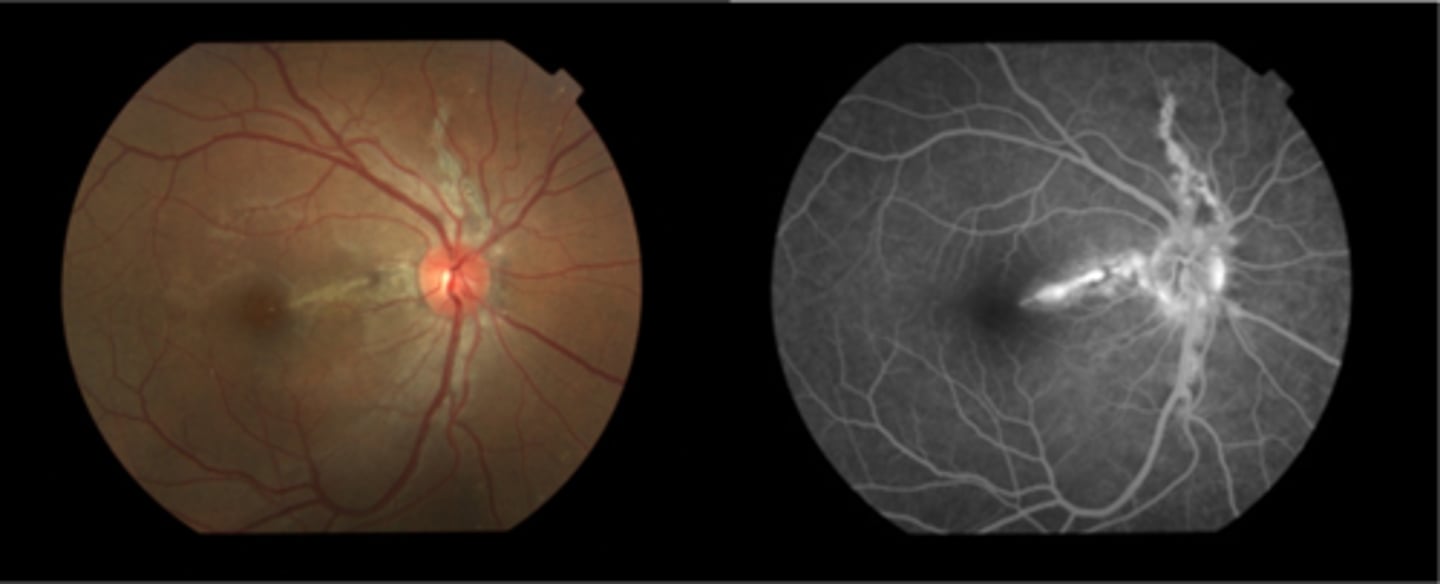

What are angioid streaks and what type of atrophy do they lead to?

breaks in Bruch's membrane in a radiating fashion emanating from the ONH = leads to RPE, PR's, choriocapillaris atrophy

What causes angioid streaks?

weakened, calcified Bruch's membrane, often in connective tissue disease = bilateral

What are the 5 CT diseases associated with angioid streaks?

PEPSI:

Pseudoxanthoma elasticum

Ehlers-Danlos syndrome

Paget's disease (of bone)

Sickle cell disease (and other hemoglobinopathies)

Idiopathic

THINK: Angie likes to drink PEPSI

How do angioid streaks affect VA?

often asymptomatic as does not involve macula

What are 2 possible complications of angioid streaks?

CNV

choroidal rupture

How do we manage angioid streaks?

educate on potential CNV or choroidal rupture, esp with injury = polycarbonate, reduced contact sports

Amsler for home monitoring

refer for CT disease workup if not already diagnosed

How does angioid streaks appear on IVFA?

hyperF bc loss of RPE = can see choroid better

How does angioid streaks appear on FAF?

hypoAF bc RPE loss/damage

What ONH finding is sometimes seen with angioid streaks?

disc drusen